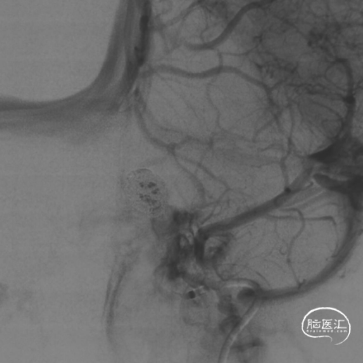

造影评估证实左侧眼动脉段动脉瘤,标记测量动脉瘤最大径13mm,动脉瘤颈5.6mm;近端血管直径4.3mm,远端3.8mm,后交通至海绵窦段后部长度24mm。压颈显示前交通开放。

选择合适工作角度。

SL-10塑形后填入Target 16/50,14/50两枚弹簧圈。

撤掉SL-10微导管后XT-27微导管置于大脑中动脉。

动脉瘤大部栓塞,瘤颈部造影剂滞留。